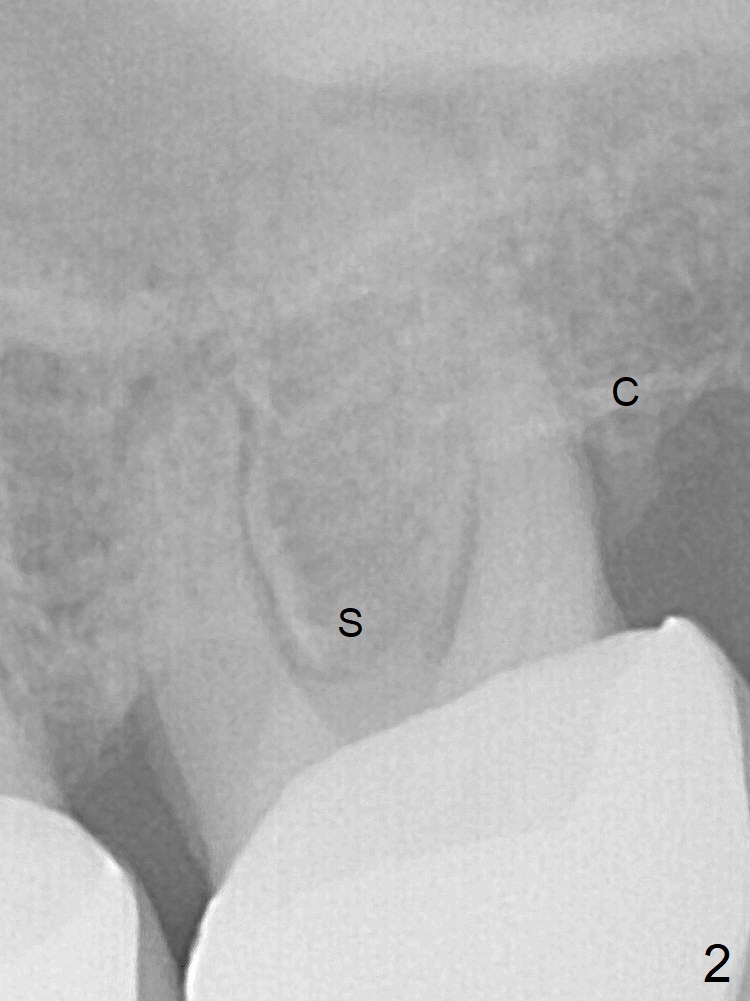

Septum Lower Than Crests

A 53-year-old man requests extraction of the tooth #14 (Fig.1) with pathology mainly around the distobuccal root. It appears that the septum (Fig.2 S) is lower than the crests (C), particularly distally, which is consistent clinically. After placement of Vanilla bone in the thin sockets (relatively large septum, Fig.3), collagen plug and sutures keep the bone graft in place (Fig.4).